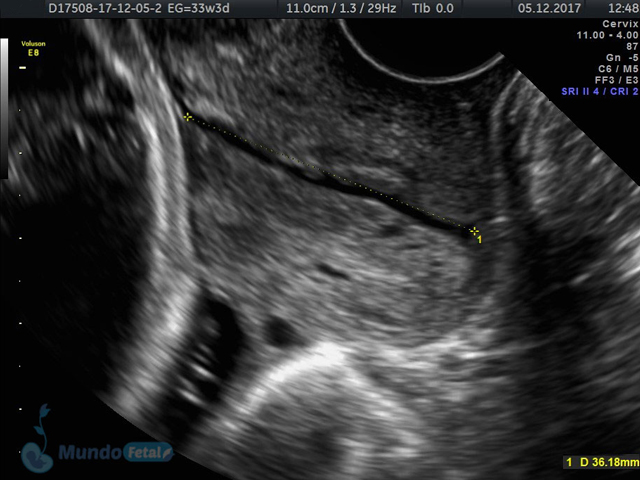

Se recomienda de 32-34 semanas, realizando valoración de crecimiento armónico (4 medidas específicas), valoración anatómica, líquido amniótico, flujos sanguíneos fetales y placentarios perfilando el bienestar fetal hacia el final de embarazo.